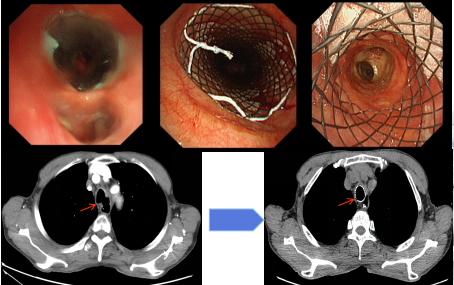

Y型支架置入术